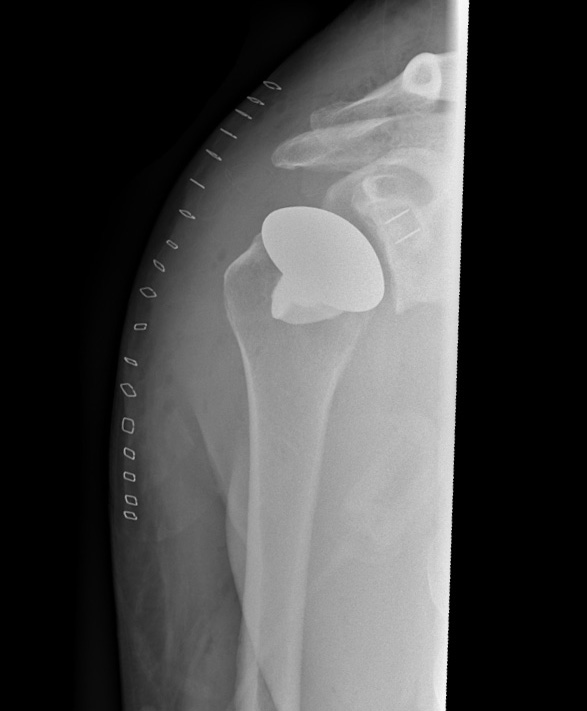

En anatomisk totalprotes ersätter de skadade ledytorna med nya i metall och plast. Denna protes efterliknas kroppens normala anatomi och förutsätter att axelns småmuskler är intakta.